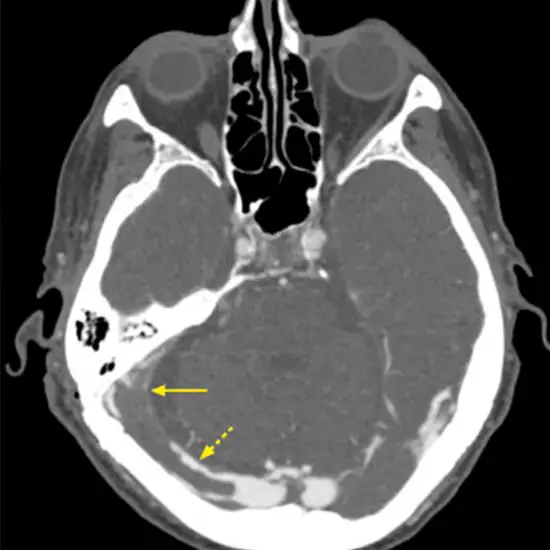

The mastoid bone is a posterior part of the temporal bone located behind the ear. NCCT (Non-Contrast Computed Tomography) Mastoid is an imaging procedure that is used to create a picture of the mastoid bone, the structure of the ear, and its surrounding tissues.